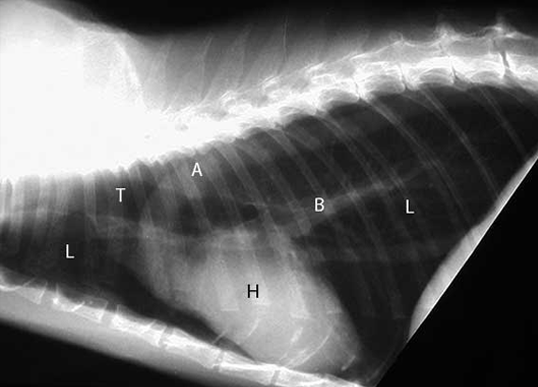

호흡기내과

호흡기 내과는 호흡기계를 구성하는 주요장기인 기도, 폐심질, 폐혀로간, 흉막 및 흉벽에 발생하는 질병들을 진단하고 치료하는 진료과입니다.

관련 주요 임상증상으로는 기침, 호흡곤란, 객혈, 무기력 등이 있습니다.

호흡기내과 주요 질환

증상 치료 폐렴, 기관/기관지염, 기관협착, 기관지 협착, 고양이 천식 흉부 방사선 검사, 투시 검사, 관련 샘플 및 배양검사, 호흡기 종양 세포 흡인 검사